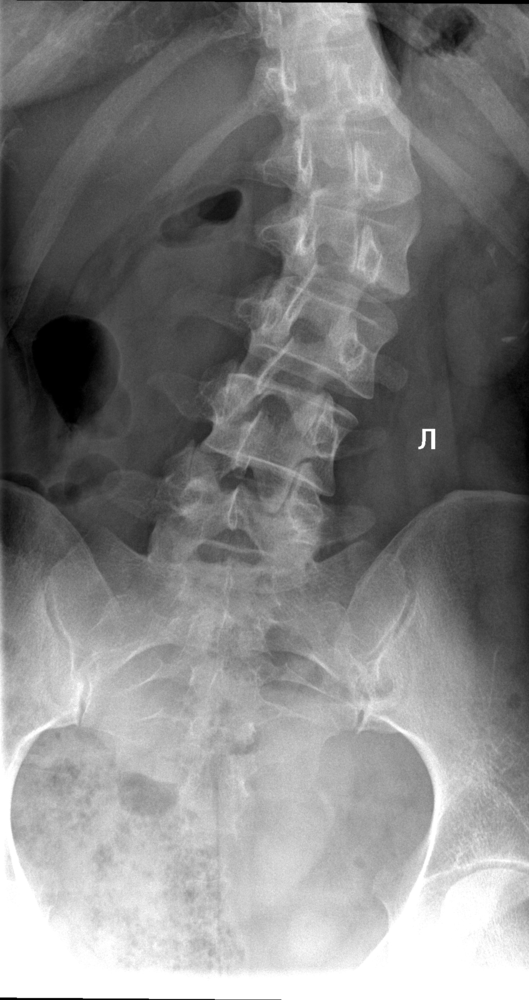

ИИ и алгоритмы интеллектуального анализа рентгеновских снимков позвоночника. Позволяет обнаружить математически обоснованные искривления позвоночника и костные аномалии менее чем за 30 секунд